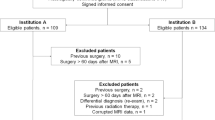

All study patients were initially diagnosed with glioma, 141 from the Cancer Genome Atlas and 131 from our tertiary institution, as training and validation sets, respectively. Images were analyzed by three neuroradiologists with 1–7 years of experience. MRI features including contrast enhancement pattern, necrosis, margin, edema, T2/FLAIR mismatch, internal cyst, and cerebral blood volume higher than normal cortex were reported using a structured reporting system. The pathology was stratified into five risk types: (1) oligodendroglioma, isocitrate dehydrogenase [IDH]-mutant, 1p19q co-deleted; (2) diffuse astrocytoma, IDH-mutant, grade II–III; (3) glioblastoma, IDH-mutant, grade IV; (4) diffuse astrocytoma, IDH-wild, grade II–III; and (5) glioblastoma, IDH-wild, grade IV. Significant predictors were selected using multivariate logistic regression, and diagnostic performance was tested using a validation set.